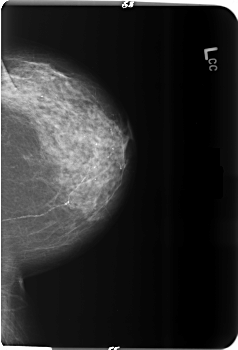

B_3513_1.LEFT_CC

LEFT_CC LINES 5936 PIXELS_PER_LINE 4040 BITS_PER_PIXEL 12 RESOLUTION 50 NON_OVERLAY

FILE: B_3513_1.RIGHT_CC.OVERLAY

TOTAL_ABNORMALITIES 2

ABNORMALITY 1

LESION_TYPE MASS SHAPE ARCHITECTURAL_DISTORTION MARGINS ILL_DEFINED-SPICULATED

ASSESSMENT 4

SUBTLETY 3

PATHOLOGY MALIGNANT

TOTAL_OUTLINES 1

BOUNDARY

ABNORMALITY 2